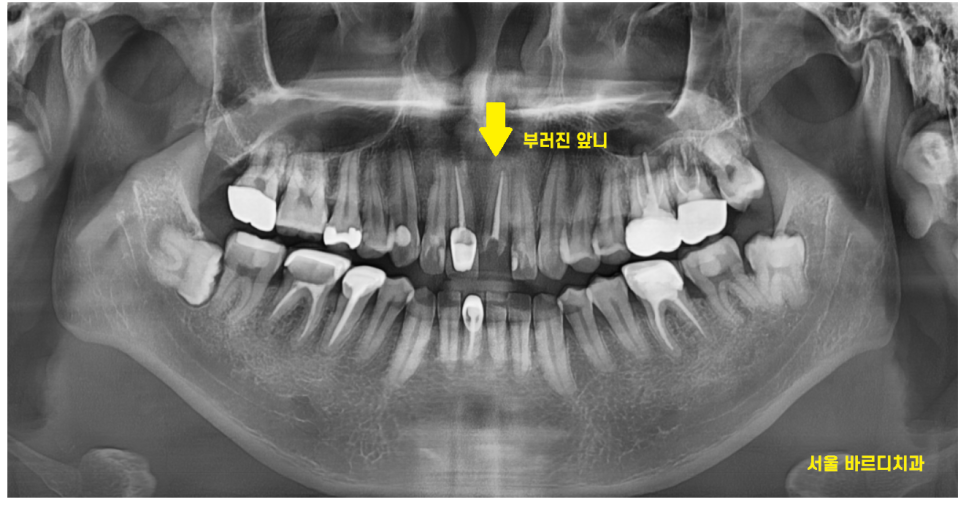

큰 x-ray로 확인을 해보니..

여지없이 신경치료가 되어 있는 상황

23.12.26

작은 x-ray로 한 번 더 확인해 보았습니다.

2/3 이상 머리가 없어졌네요..

앞니 부러짐 치료의 방향을 결정할 때에는

남아있는 치아의 양이 중요합니다.

살릴 수 있을지 없을지

예후를 결정하는

key point이죠!!

잇몸뼈에 뿌리만 박혀있는 수준이라

발치 후 임플란트 계획을

잡아드렸습니다.